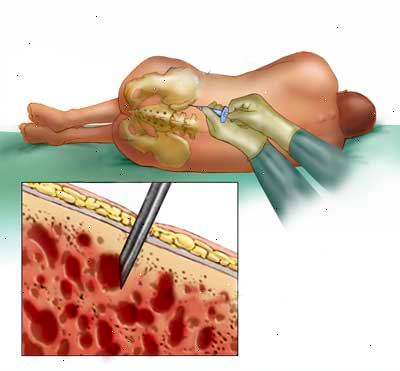

Cirurgia endovascular

Cirurgia que realiza o tratamento de doenças circulatórias por meio de cateteres, guias, balões, stents e endopróteses.

- Tratamento com cateteres e guias

- Implante de stents e endopróteses

- Menor trauma cirúrgico